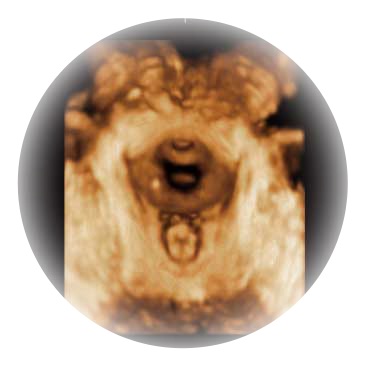

宽频带腹部凸阵探头和腹部容积探头、大角度腔内探头和腔内容积探头、独特的生殖专用曲柄探头,为妇产应用提供全面诊疗方案。

大角度腔内容积探头,可完整包络子宫及盆底结构,充分展示组织结构毗邻关系。